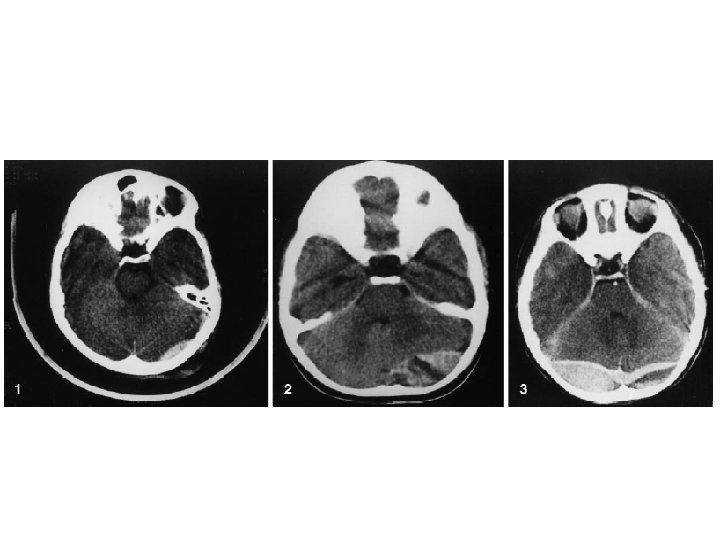

EDH ‘da BT’de bikonveks ( lentiküler ) görünüm

Subdural Hematom (SDH) • • Travma sonrası parenkim laserasyonu Yüzeyel veya asıcı venlerin kopması BT’de konkav görüntü Başvuru sırasında nörolojik tablo EDH’a göre daha kötü • Mortalite çok daha yüksek % 50 -60’lara kadar çıkabilir